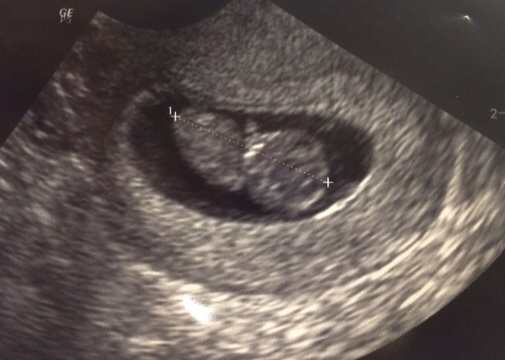

I finally had my first appointment today! Everything looks amazing! Baby is measuring perfectly at 9w3d, 180 heartbeat and due date is still Feb 28th! So relieved that everything is going as planned! These last weeks were hell! Here's the little peanut! Xxxxxx